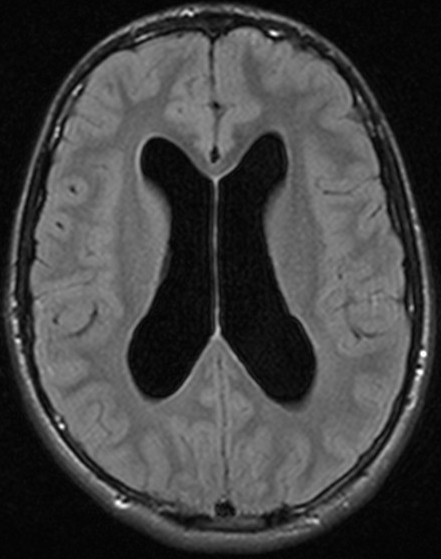

Гидроцефалия

Ведущую роль в диагностике гидроцефалии играют:

• КТ

• МРТ